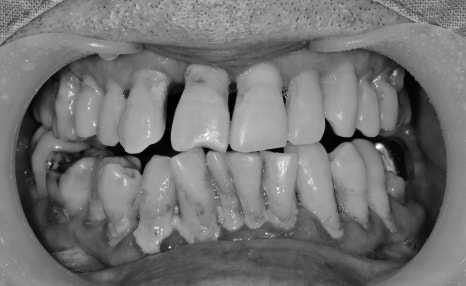

구강 내 사진을 보게 됐을 때

정상 잇몸 레벨에서 치은염의 진행으로 잇몸이 많이 내려앉은 상태에서

더욱 깊게 양치가 어렵다 보니 치주염으로 이미 진행이 된 상태였습니다.

다수 치아의 발치가 필요하지만 치료 진행과 더불어 중요한 것은 잇몸 관리였습니다.